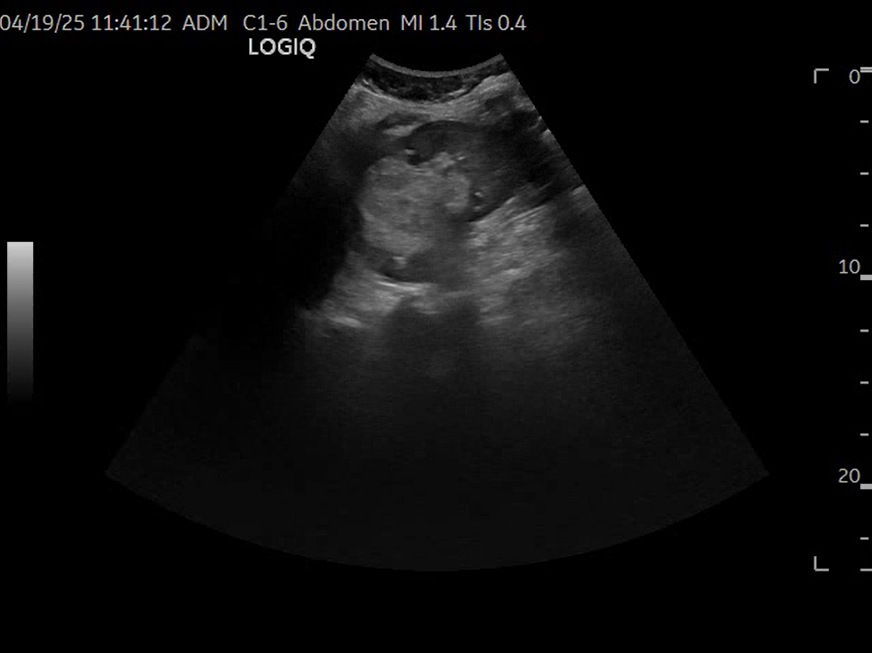

Se realiza ecografía clínica objetivando esteatosis hepática así como litiasis en vesícula biliar que mide 1,6 cm sin signos de complicación. A nivel del riñón derecho presenta lesión hiperdensa en zona media y polo inferior que no capta con realce, sin apreciarse dilatación de cáliz. Se consulta con radiólogo de guardia que indica realizar TAC abdominal para filiar.

Por tanto, se prescribe analgesia y se completa estudio con TAC abdominal de forma ambulatoria con cita preferente a Cirugía General y Urología. En el TAC se describe masa heterogénea sólida con áreas de degeneración quística/necrótica y calcificaciones groseras sin demostrar grasa macroscópica en mitad superior del riñón derecho compatible con carcinoma de células renales, y nódulo con focos grasos en la cortical de la mitad inferior del riñón derecho compatible con angiomiolipoma.